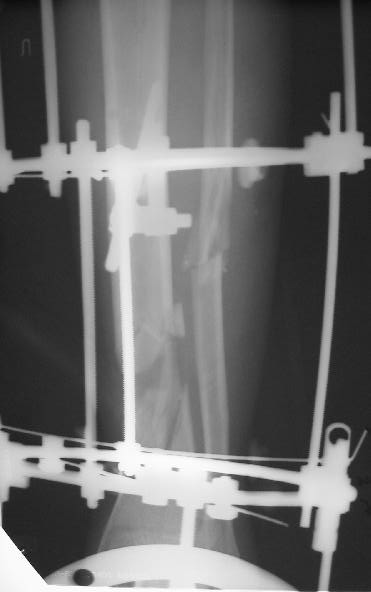

Больного прооперировал, обработку мягких тканей на голени не стал делать, думаю, некроз по краю швов на голени заживет под струпом (рис 3). На стопе удалил некротические ткани, готовлю ее к аутопластике (рис 2).

На дополнительных снимках итраоперационно видна значительная потеря массы (рис 6 рис 1). Хотя на снимках контрольных после операции вроде дефекта значительного нет. Все же придется, как-то замещать дефект костный на голени, думаю подготовить морально больного к повторной операции костной пластике, после заживления ран.